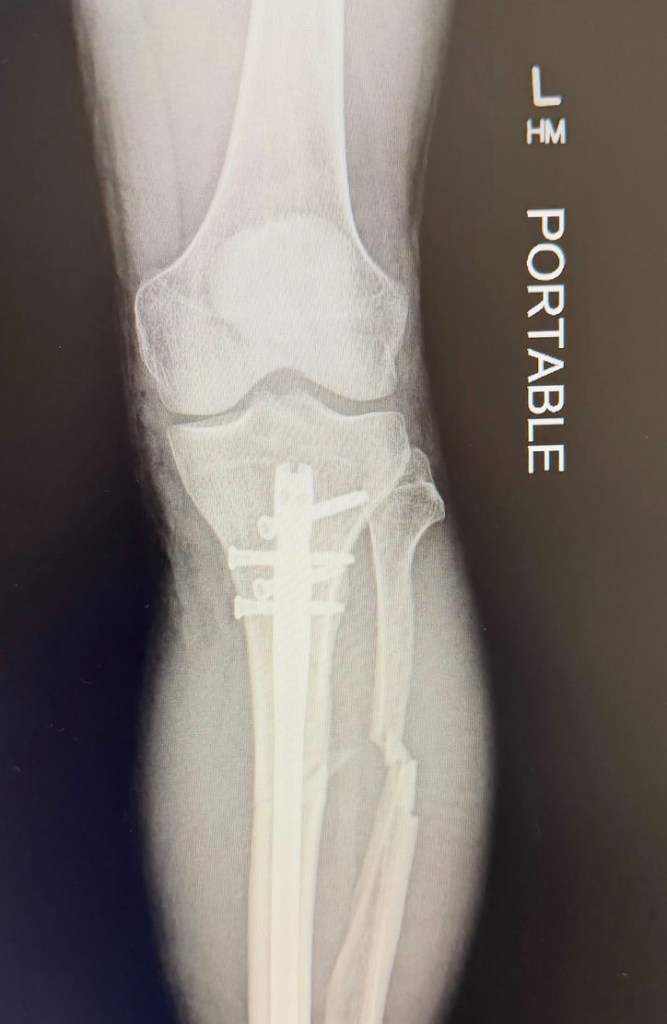

Texas musician, YouTuber, and all-around wacky guy Marc Rebillet, or “Loop Daddy” as he’s affectionately known, posted several Instagram photos yesterday. They showed him in a hospital bed and included an X-ray revealing a rather gruesome break.

“We had to end the tour early because I had a stupid accident on my scooter and snapped my leg in half,” Rebillet wrote alongside the snaps of his snapped leg. “It’s a bad injury, but man…I’ve had the most wonderful people around me to keep me from going insane.”